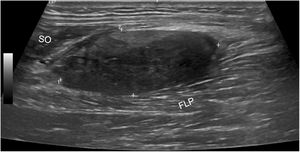

A musculoskeletal ultrasound showed a solid 3.5 × 1.5 cm tumor with well-defined margins, localized in the soleus muscle, with a predominantly hypoechoic heterogeneous structure with intralesional and perilesional vascularization (Fig. 1). An MRI confirmed the presence of a solid and deep tumor in the posterior compartment of the distal end of the calf, of characteristic fibrous origin (Fig. 2). An ultrasound-guided biopsy evidenced histological lesions characteristic of a rheumatoid nodule (Figs. 3 and 4). The suggested therapy was intralesional infiltration with depot corticosteroid preparation; however, since the lesion was asymptomatic and its size shrunk in the control ultrasound, the patient dismissed the procedure.

Ultrasound image of the posterior margin of the calf, with a solid nodule with well-defined margins (marked between calipers), of heterogeneous structure, mostly hypoechoic, with no cystic areas or peritumoral edema, localized between the muscle belly of the flexor digitorum longus (FLP) and the soleus (SO).